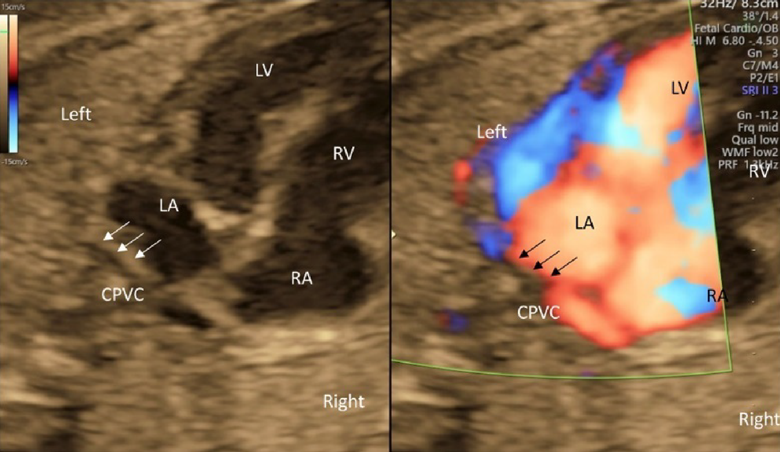

- The connection of the left and the right pulmonary veins to the left atrium should be confirmed by tomographic ultrasound, color Doppler ultrasound, and pulmonary venous pulsed Doppler waveforms. The pulsed Doppler waveforms of the pulmonary veins are normally bimodal. The waveforms would be unimodal or flat in fetuses with total anomalous pulmonary venous return or pulmonary venous stenosis. Also, the former should be suspected when the distance between the posterior wall of the left atrium and the descending aorta is greater than normal.55)